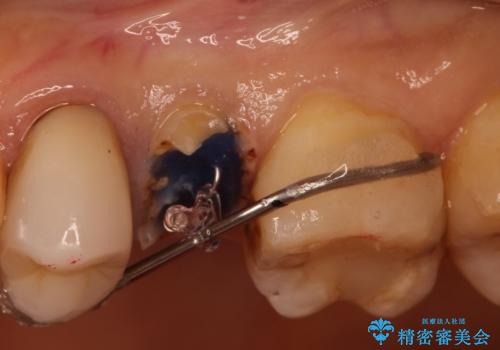

かぶせ物と詰めてある修復物を除去すると歯肉の中まで虫歯になっていました。

歯を部分矯正で引き上げて、虫歯を徹底的に取り除き、適合の良いかぶせ物を装着する計画としました。

深い虫歯の治療は、治療が長期化したり、困難になることがあります。